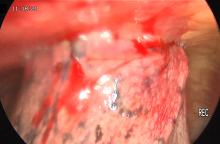

Hybrid Uniportal VATS Technique for Left Upper Lobectomy With Chest Wall Resection and Reconstruction [1]

A 60-year-old patient was diagnosed with a T3N0M0 squamous cell carcinoma. A multidisciplinary tumor board decided to perform a hybrid procedure of left upper lobectomy with resection of three involved ribs. The course of the surgery was uneventful, and the patient was discharged home on postoperative day five.